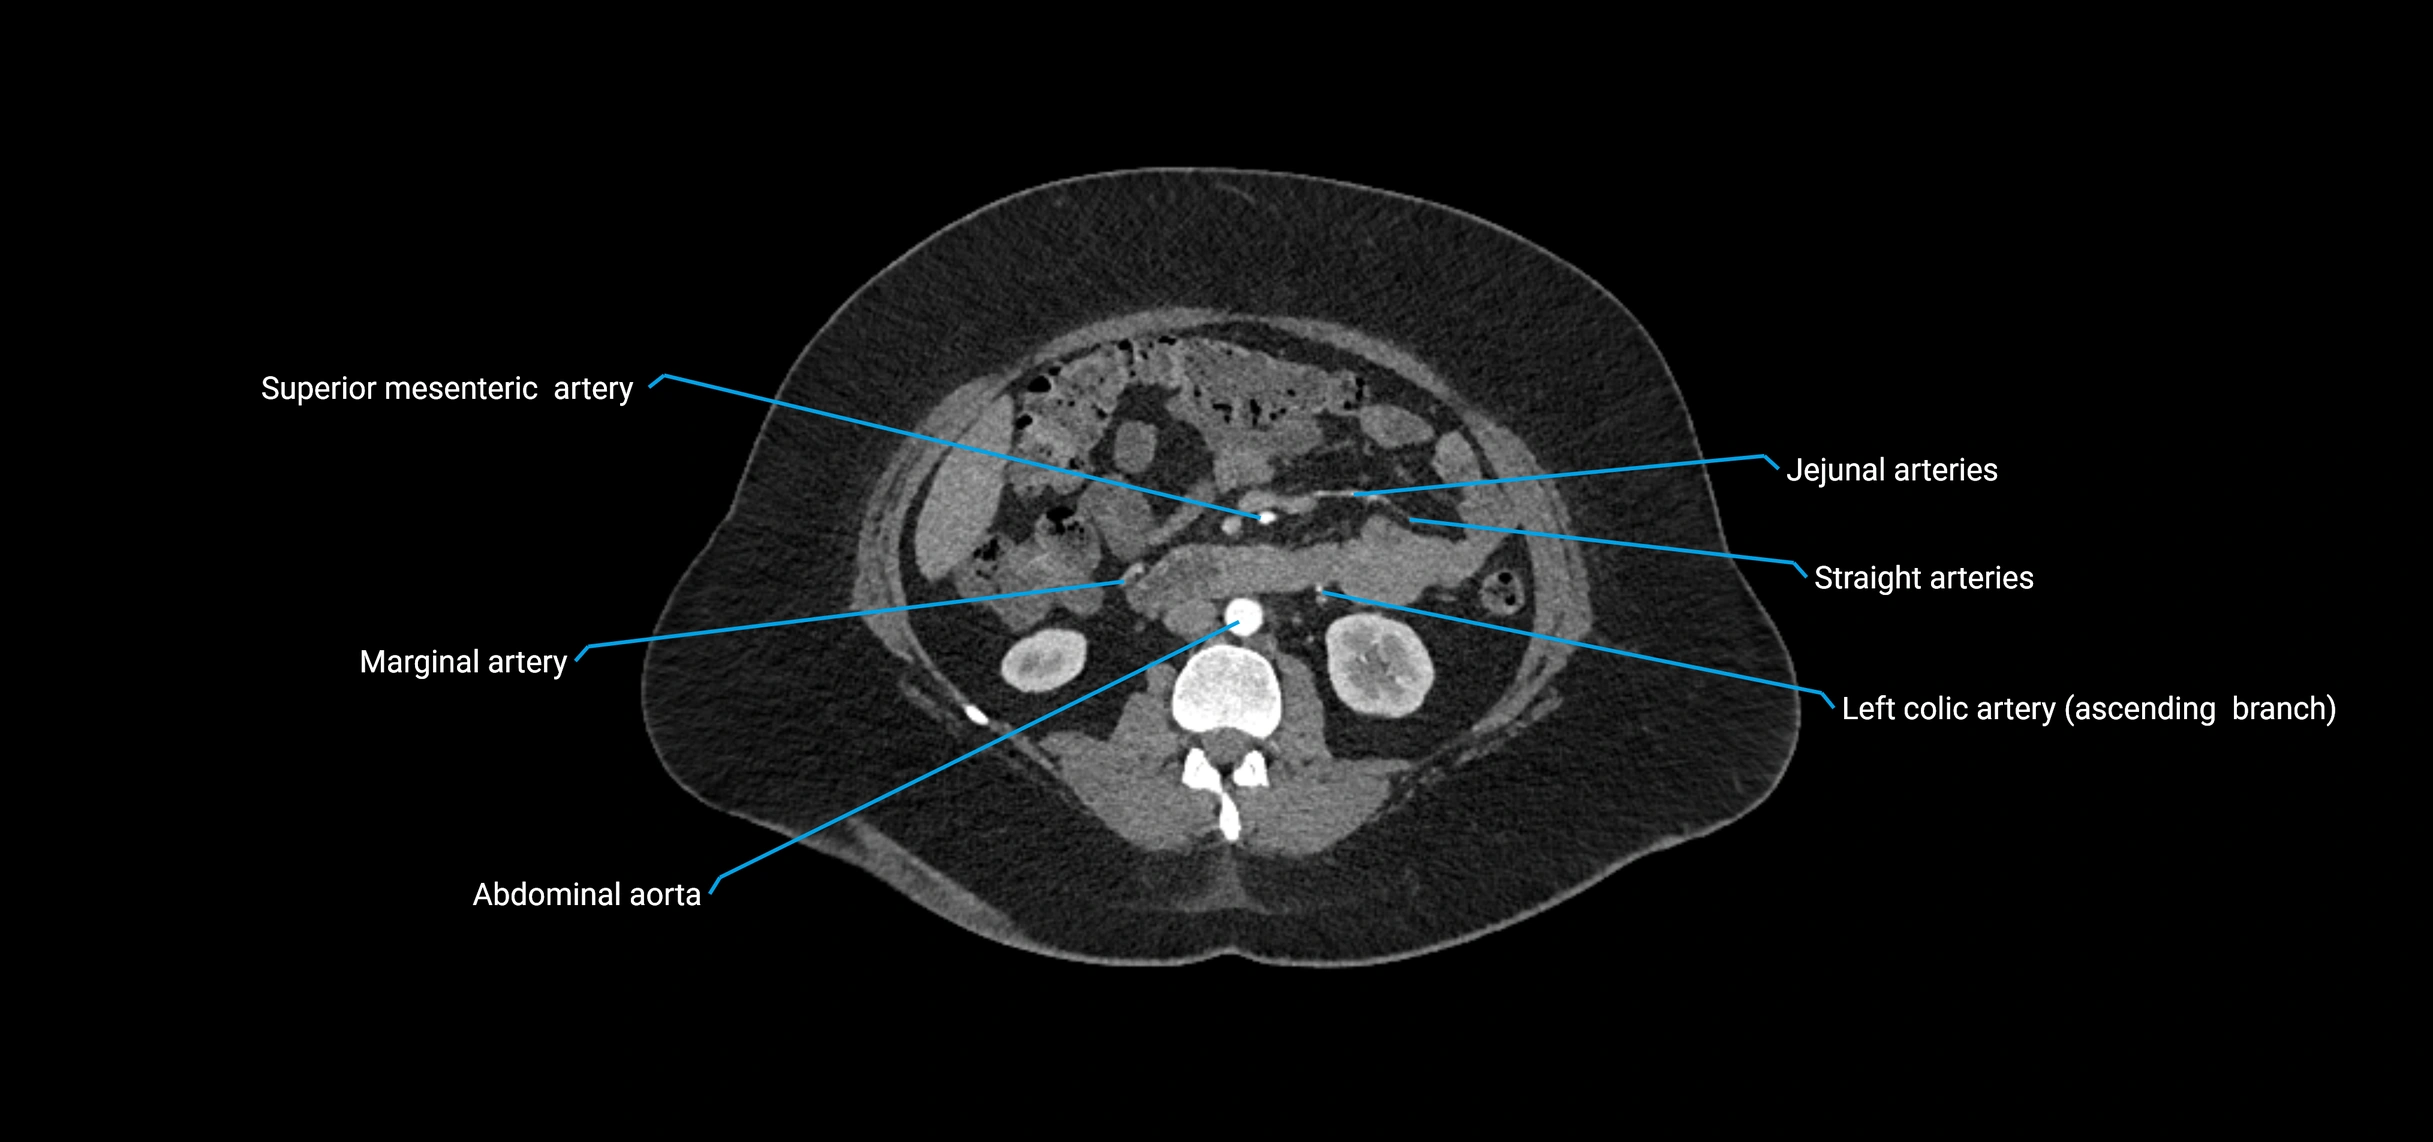

Contrast-enhanced CT (CTA):

• Gold standard for abdominal aortic imaging

• Provides excellent detail of lumen, wall, aneurysm, thrombus, and branch vessels

• Multiplanar and 3D reconstructions help in aneurysm measurement, stent graft planning, and dissection evaluation